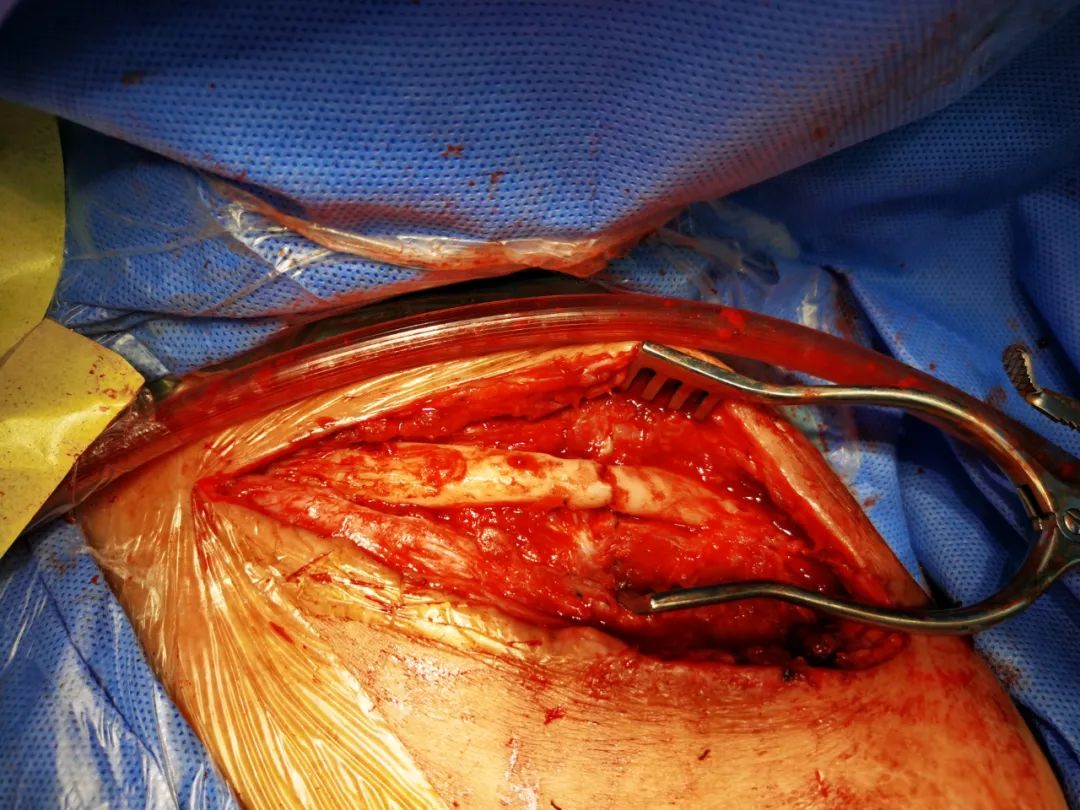

手术经过

术中可见锁骨骨皮质连续性中段,清理断端死骨以及硬化骨后,切取自体髂骨进行植骨,再次用钢板固定。

手术经过:滑动看 !!!

术后复查锁骨对位对线良好。